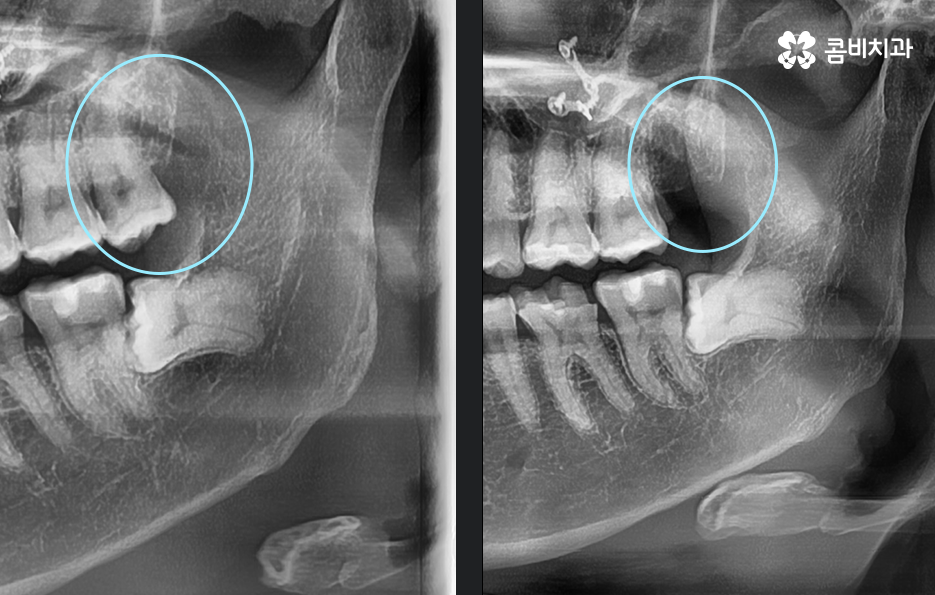

꼭 청결 관리의 이슈가 아니더라도 사랑니가 자라는 위치나 방향 자체가 좋지 않은 경우에는 문제가 예상되기 때문에 미리 발치하거나 이미 문제가 진행되고 있는 경우에는 사랑니 발치 시기 놓치지 말아야 더 큰 문제로 이어지는 일을 막을 수 있는데요.

현대인들은 사랑니의 위치가 좋지 않아서 주변 치아와 잇몸에 염증이 발생되는 사례가 많고 특히 하악에 매복 사랑니가 있는 경우가 많은데 완전히 누워서 자라는 사랑니는 발치 자체도 어렵지만 뿌리가 깊어지기 전에 발치하는 것이 발치나 회복에도 수월하기 때문에 정확한 사랑니 발치 시기의 골든타임을 놓치지 않기 위해서도 사랑니가 나올 무렵에 자신의 사랑니가 어떻게 자라고 있는지 확인하실 필요가 있어요